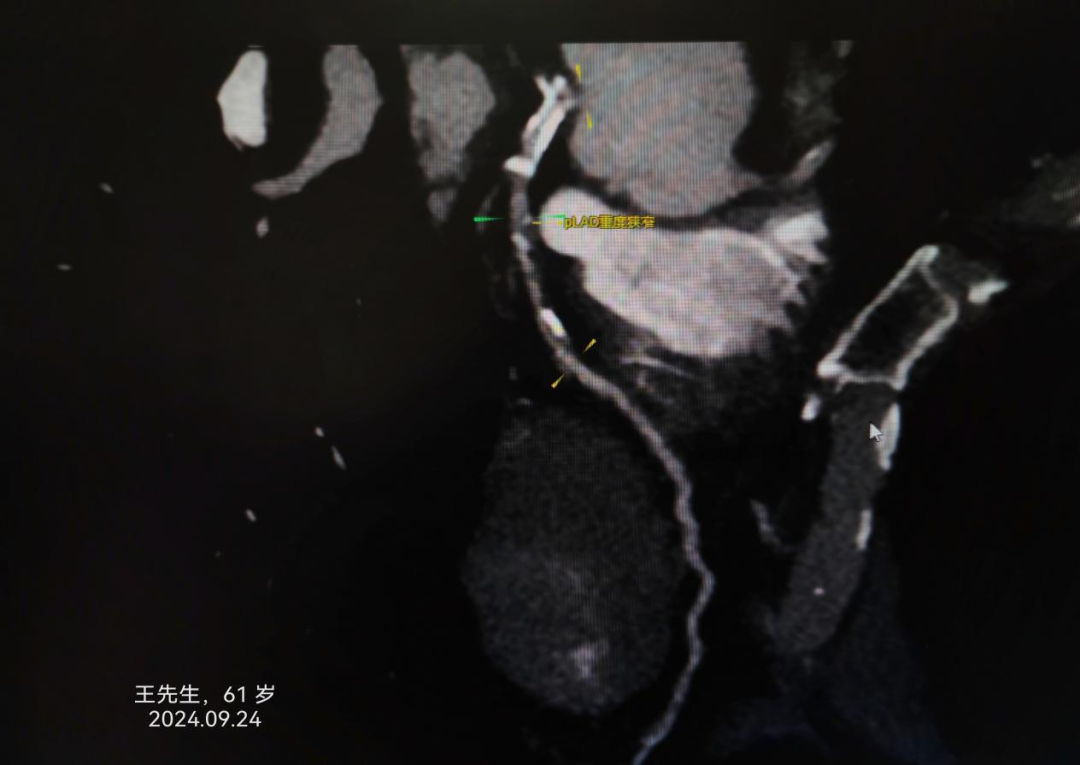

病例1:王先生,61岁,诊断“不稳定型心绞痛”。

寿光和信医院目前引进的中国联影640排高端螺旋CT天河960+,对冠脉成像有独特的优势,可无限制心脏成像,单心跳-高心率冠脉成像、单心跳-严重心律不齐、单心跳-自由呼吸扫描,成像效果极佳,与冠脉造影结果差距极小,并且检查时间3-5分钟、较之前缩短75%。部分冠脉CTA、冠脉造影结果对比如下: